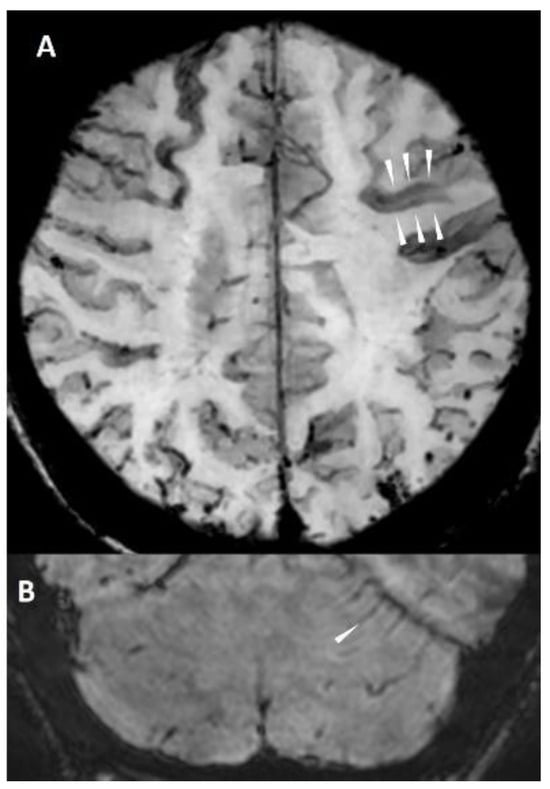

6.1. Finger-like Projections

- Renard, D.; Parvu, T.; Thouvenot, E. Finger-Like Projections in Lobar Haemorrhage on Early Magnetic Resonance Imaging Is Associated with Probable Cerebral Amyloid Angiopathy. Cerebrovasc. Dis. 2019, 47, 121–126. [Google Scholar] [CrossRef]

- Baron, J.-C.; Jensen-Kondering, U.; Sacco, S.; Posener, S.; Benzakoun, J.; Pallud, J.; Oppenheim, C.; Varlet, P.; Turc, G. Can novel CT-and MR-based neuroimaging biomarkers further improve the etiological diagnosis of lobar intra-cerebral hemorrhage? J. Neurol. 2023, 270, 582–588. [Google Scholar] [CrossRef]